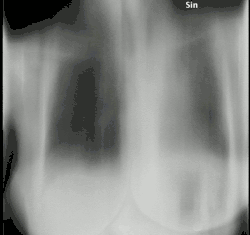

Tomosynthesis, also digital tomosynthesis (DTS), is a method for performing high-resolution limited-angle tomography at radiation dose levels comparable with projectional radiography. It has been studied for a variety of clinical applications, including vascular imaging, dental imaging, orthopedic imaging, mammographic imaging, musculoskeletal imaging, and chest imaging.[1]

Digital tomosynthesis combines digital image capture and processing with simple tube/detector motion as used in conventional computed tomography (CT). However, though there are some similarities to CT, it is a separate technique. In modern (helical) CT, the source/detector makes at least a complete 180-degree rotation about the subject obtaining a complete set of data from which images may be reconstructed. Digital tomosynthesis, on the other hand, only uses a limited rotation angle (e.g., 15-60 degrees) with a lower number of discrete exposures (e.g., 7-51) than CT. This incomplete set of projections is digitally processed to yield images similar to conventional tomography with a limited depth of field. Because the image processing is digital, a series of slices at different depths and with different thicknesses can be reconstructed from the same acquisition. However, since fewer projections are needed than CT to perform the reconstruction, radiation exposure and cost are both reduced.[4]

Digital breast tomosynthesis (DBT)[5] is Food and Drug Administration (FDA) approved for use in breast cancer screening.[6] The benefit for screening has been debated,[7] but consensus is being reached that the technology is improving sensitivity compared to two-view digital mammography at the cost of a slightly reduced specificity (increased recall rates).[8] Because the data acquired are 85 - 160 micron typical resolution, much higher than CT, DBT is unable to offer the narrow slice widths that CT offers (typically 1-1.5 mm). However, the higher resolution detectors permit very high in-plane resolution, even if the Z-axis resolution is less. Another interesting property of breast tomosynthesis is that image quality may vary substantially through the imaging volume.[9] DBT reading times are much higher, compared to mammography interpretation.[10]